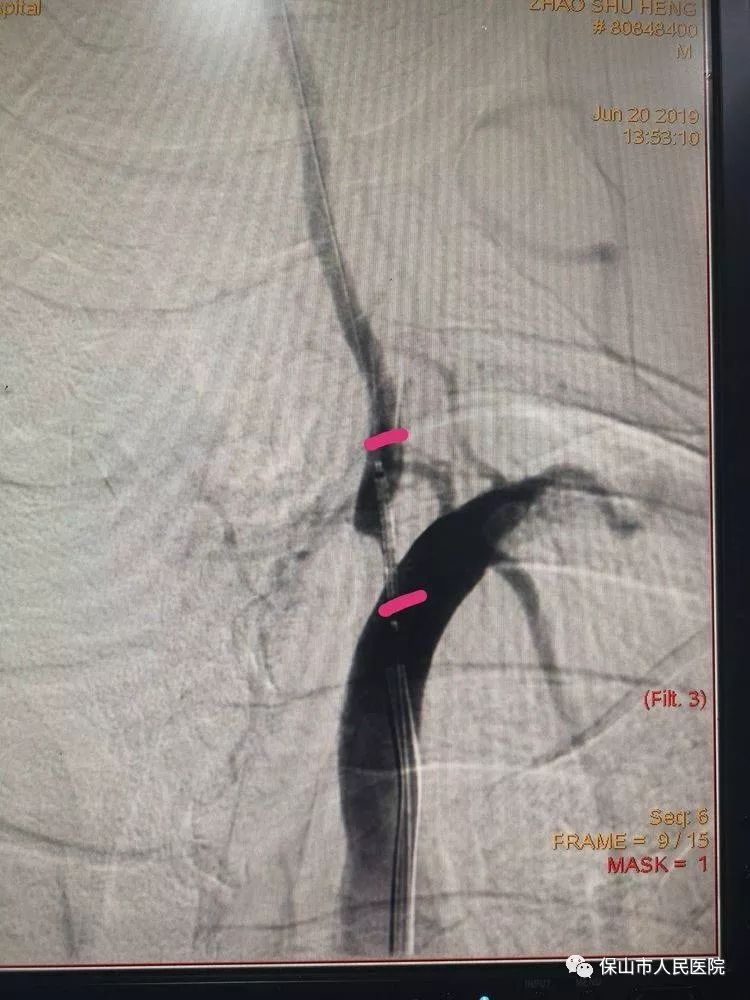

通過導絲(si) 和導管的配合,將支架放在狹窄的部位,如圖中兩(liang) 個(ge) 標記點之間,然後再釋放支架,把狹窄部位支撐開。